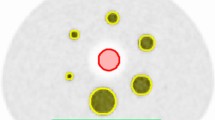

Assessing PET image quality (IQ) remains a challenge due to its clinical subjectivity and difficulties in standardisation. Over the years, there have been described at least four different methods to evaluate the PET image quality: image noise, noise equivalent count rate (NECR), NEMA NU-2 image quality phantom measurements and visual IQ.

The first two are automatic and objective measurements determined from the reconstructed image or PET raw emission data of phantoms.

In a first step, all data were automatically analysed using Matlab (MathWorks, Natick, MA, USA) to estimate the NECR versus activity concentration in a similar manner to the National Electrical Manufacturers Association (NEMA) analysis and based on previous publications [8]-[12]. This measurement is essentially the same usually performed on phantom data, but the required data (the number of true, scattered and random counts) are estimations either provided by the scanner software or automatically extracted from the reconstructed image. To determine the NECR for a bed position of patient data, the following steps were used: the PET raw data files were used to measure prompts and to calculate randoms from singles and obtain the bed position duration. Then, the reconstructed PET images were used to obtain an estimate of the model-based scatter fraction. With those two items, the NECR was calculated for each bed position, and the patient NECR was an average of all whole-body bed positions. By using the PET images, voxels above a fixed activity concentration of 1.0 kBq/mL, the average activity concentration for all voxels in the bed position was calculated. Decay to each bed position based upon its start time relative to scan start was applied as well.